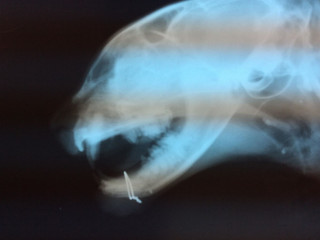

| 特徴(性格など) | 仮名を『蛍』といいます。 サビ柄の女の仔です。 センター収容猫です。 尻尾の先が蛍の光みたい。チャームポイントです。 快食快便、健康状態は良好です♪ 現在は元気いっぱいの蛍も、交通事故に遭い顔面を負傷してセンターに収容されていました。 首輪の跡がくっきり....不妊手術も施されていました。 人間に寄り添い生きていた仔、お家の仔だったと思われます。 引き出し後その足で受診をしまして、そのまま入院となりました。 下顎骨折もあったため手術をしています。 それでも最初のうちは口が閉まらず、フードも自力では食べられなかったのですが、 蛍の生命力を感じる場面は、入院中も退院後も所々にみられました。 下顎にピンが入っていますが、このままでも大丈夫とのことです。 時々舌が出っ放しになってしまうのと、多少顎がずれてしまっていますが、 現在は食べること飲むこと問題なく、ドライフードも食べています。 他猫が大好きです♪ 猫見知りありません。とにかくとても優しい仔です。 人間にはちょっとビビリですが、ナデナデが好きで、 気がつくとそっと足元に寄り添っているような、温和で控えめな仔です。 お留守番も問題なく過ごせています。 蛍が家族の一員に加わることで、共に幸せを感じていってもらえたら嬉しいです。 可愛い蛍に会いにいらしてください。 【医療処置情報】これから実施のも含まれます *健康チェック *3種混合ワクチン接種 *ウイルス検査実施(FIV.FeLV共に陰性) *検便実施 *駆虫薬投与(レボリューション、ドロンタール) *マイクロチップ装着 *不妊・去勢手術 |